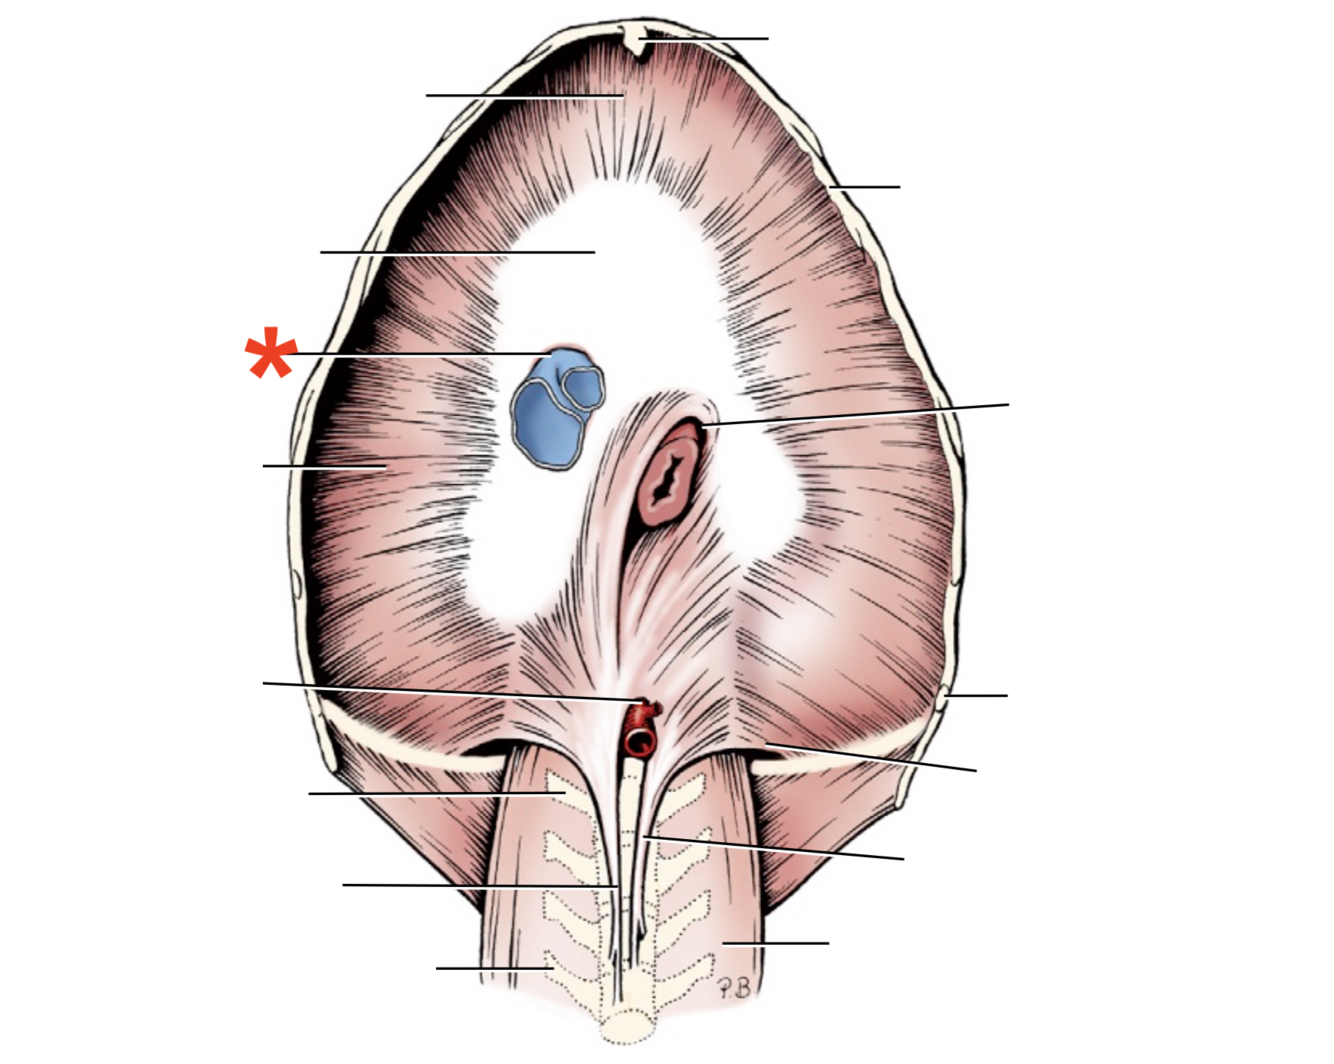

1

Q

Name given to the most cranial part of the diaphragm.

A

Cupula Diaphragmatis

2

Q

A

Pars sternalis

3

Q

A

Foramen vena cavae

4

Q

A

Pars costalis

5

Q

A

Hiatus aorticus

6

Q

A

Arcus lumbocostalis

7

Q

A

Hiatus oesophagus

8

Q

A

Crus sinistrum

9

Q

A

Crus dextrum

10

Q

A

Centrum tendineum

11

Q

A

Corona muscularis